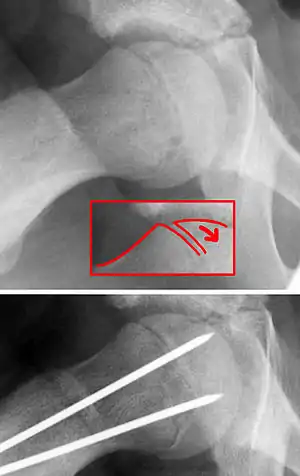

![]() | |

| X-ray showing a slipped capital femoral epiphysis, before and after surgical fixation. | |

The diagnosis requires x-rays of the pelvis, with anteriorposterior (AP) and frog-leg lateral views.[9] The appearance of the head of the femur in relation to the shaft likens that of a "melting ice cream cone", visible with Klein's line. The severity of the disease can be measured using the Southwick angle.

The disease can be treated with external in-situ pinning or open reduction and pinning. Consultation with an orthopaedic surgeon is necessary to repair this problem. Pinning the unaffected side prophylactically is not recommended for most patients, but may be appropriate if a second SCFE is very likely.[9]

Once SCFE is suspected, the patient should be non-weight bearing and remain on strict bed rest. In severe cases, after enough rest the patient may require physical therapy to regain strength and movement back to the leg. A SCFE is an orthopaedic emergency, as further slippage may result in occlusion of the blood supply and avascular necrosis (risk of 25 percent). Almost all cases require surgery, which usually involves the placement of one or two pins into the femoral head to prevent further slippage.[10] The recommended screw placement is in the center of the epiphysis and perpendicular to the physis.[11] Chances of a slippage occurring in the other hip are 20 percent within 18 months of diagnosis of the first slippage and consequently the opposite unaffected femur may also require pinning.

The risk of reducing this fracture includes the disruption of the blood supply to the bone. It has been shown in the past that attempts to correct the slippage by moving the head back into its correct position can cause the bone to die. Therefore the head of the femur is usually pinned 'as is'. A small incision is made in the outer side of the upper thigh and metal pins are placed through the femoral neck and into the head of the femur. A dressing covers the wound.